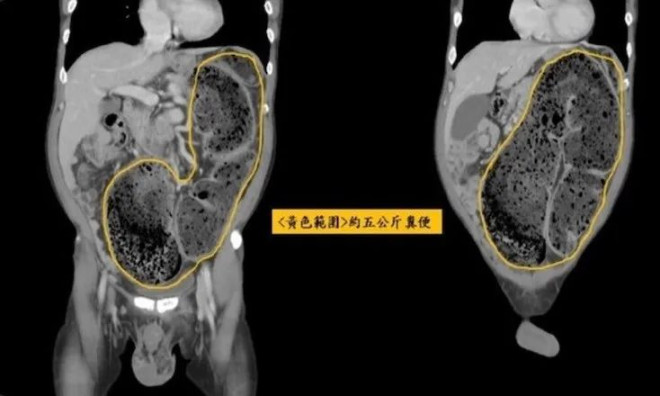

一个人长时间便秘,会诱发怎样的严重后果?可能导致腹痛或肋部痛疼,还可能把大肠顶入胸腔,出现“大便攻心”的罕见场面。最近,泰国医生Phi Da就分享了这样一个病例,警示大家便秘的危害。 ![]() (Phi Da医生) 有一位23岁的中国台湾女性A,不久前患上了便秘,一开始她并没有放在心上。没想到情况越来越严重,A女士的便秘时间越拖越长,最后竟持续长达17天没有排便…A女士逐渐感觉腹腔和肋部疼痛,之后又感觉些许胸闷和胸腔压迫。 于是只好去医院检查,医生给A女士拍了X光片后惊讶地发现:因为长时间没有排便,A女士体内的宿便严重堆积,不仅将大肠撑到膨胀鼓起,还将大肠撑到向上高高顶起。只见A女士的大肠已经严重偏离了腹腔的原本位置,高高顶起到了胸腔位置!! ![]() (A女士的大肠被宿便顶到胸腔)也就是说,紧挨着A女士的心脏和肺下面,就是她堆积了17天的宿便团,如果不及时取出和疏导,A女士很可能面临肠道破裂,大量宿便感染腹腔乃至胸腔的风险。到那个时候,“心中有屎”就真不是一个比喻了… ![]() (大肠被宿便撑到变形拱起) 好在A女士的病情得以及时发现,在医生的要求下及时进行了手术,虽然切掉了一部分肠子,但好歹没有发生肠道破裂,“屎溅心肺”的风险…无独有偶,在A女士“大便攻心”的病例出现之前,中国台湾三年前也出现过一起类似的病例。 ![]() (2022年的类似病例报道) 58岁的男子B足足20天未能排便,去医院检查后发现,他的乙状结肠里有多达5公斤的宿便。并且堆积在结肠上不,一路顶到心脏位置,病情相当危险。最后医生给该B先生做手术,硬是用手指将粪石捏碎并挖出,才成功疏通他的肠道,缓解了他的腹胀和肠梗阻,B先生才得以转危为安… ![]() (黄色部分是重达5公斤的宿便) 对于这类病例,Phi Da医生特别强调: 这看起来如此可怕的病例,竟然是不注意日常生活习惯导致的,比如平日里喝水太少、吃蔬菜水果太少,或者习惯于憋屎,都是值得预防和注意的行为。 为了避免这样的病例出现,网友们有必要保持以下这些良好习惯: 1.每天喝足够的水。 2.吃富含膳食纤维的食物 3.保持有规律的运动 4.训练自己定时上厕所 5.不要让便秘超过2~3天 6.补充益生元,增加肠道中的有益菌,帮助改善排便。 但愿大家都能保持良好的生活习惯,及时排便,避免“宿便攻心”的惨烈场面… |